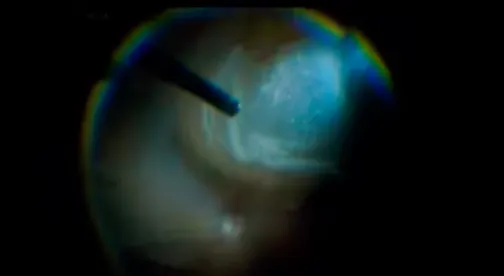

Francesco Boscia, MD, demonstrates surgery on a patient with diabetic tractional macular edema where the pathology is deceptively widespread. Following removal of multiple layers of vitreous with the aid of triamcinolone, Dr. Boscia injects a dexamethasone intravitreal implant to prevent PVR and macular edema postoperatively. Dr. Boscia takes extra precautions to avoid having the implant hit the retina.